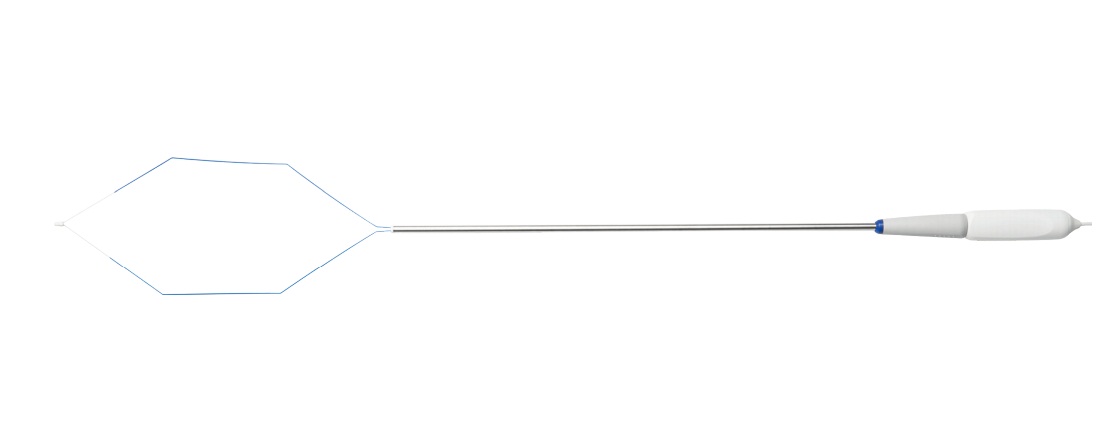

Петля для лапароскопии РК, биполярная лапароскопическая петля

Петля для лапароскопии обеспечивает повышенную безопасность пациента вкупе с быстрым, мгновенным и прямым рассечением матки во время процедур над влагалищной гистерэктомии. Особые преимущества для гинеколога, выполняющего сложную лапароскопическую операцию, заключаются

в следующем:

- Проволока с синим покрытием для оптимальной видимости при размещении петли

- Белый керамический наконечник помогает понять, попал ли кишечник в петлю

- Быстрое, чистое и мгновенное биполярное рассечение

- Большая петля для серьезных случаев

- Выдвигающаяся ромбовидная петля открывается в брюшной полости

- Стабильная форма петли

- Эргономичная конструкция рукоятки

Петля для лапароскопии РК, биполярная лапароскопическая петля

Петля для лапароскопии обеспечивает повышенную безопасность пациента вкупе с быстрым, мгновенным и прямым рассечением матки во время процедур над влагалищной гистерэктомии. Особые преимущества для гинеколога, выполняющего сложную лапароскопическую операцию, заключаются

в следующем:

- Проволока с синим покрытием для оптимальной видимости при размещении петли

- Белый керамический наконечник помогает понять, попал ли кишечник в петлю

- Быстрое, чистое и мгновенное биполярное рассечение

- Большая петля для серьезных случаев

- Выдвигающаяся ромбовидная петля открывается в брюшной полости

- Стабильная форма петли

- Эргономичная конструкция рукоятки